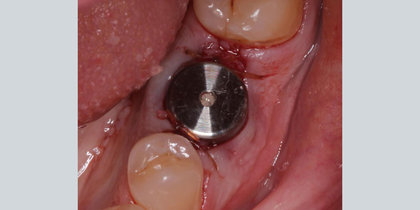

• A Glidewell HT is immediately placed into the extraction socket of a maxillary central incisor. thumbnail image

Extraction with Immediate Placement

A Glidewell HT is immediately placed into the extraction socket of a maxillary central incisor.